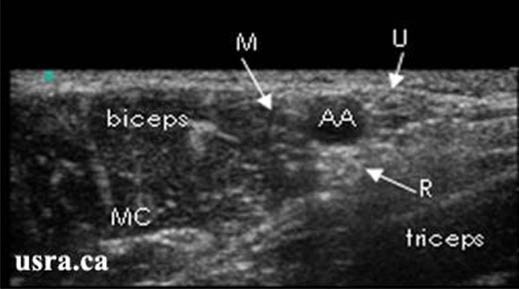

- Considerable anatomic variation is noted for all the terminal branches of the brachial plexus; however the most common orientations are shown in Figure 5.

- Median Nerve – anterior lateral to the artery (above and slightly left, at the 10 to 12 o’clock position relative to the artery)

- Ulnar Nerve – anterior medial to the artery (above and to the right, near the axillary vein, 1-3 o’clock position relative to the artery)

- Radial Nerve – posterior medial to the artery (below and to the right, between 3 to 6 o’clock positions relative to the artery)

- Musculocutaneous Nerve – optimal imaging requires more lateral positioning of the transducer as it lies within the coracobrachialis muscle or fascia just below the biceps muscle

Downloaded with permission from Ultrasound for Regional Anesthesia (2008)